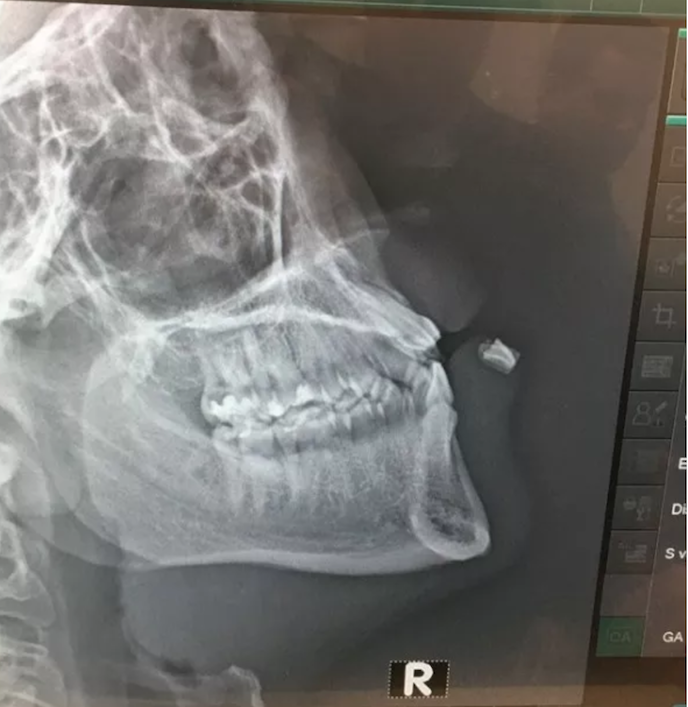

Fortunatamente il giocatore ha “solamente” perso un paio di denti, uscendo sanguintante dal ghiaccio ma facendo poi ritorno in un secondo momento indossando una speciale maschera protettiva.

Vesey ha però dovuto sottoporsi ad un intervento particolare al termine del match, visto che uno dei denti è rimasto incastrato nel suo labbro inferiore.